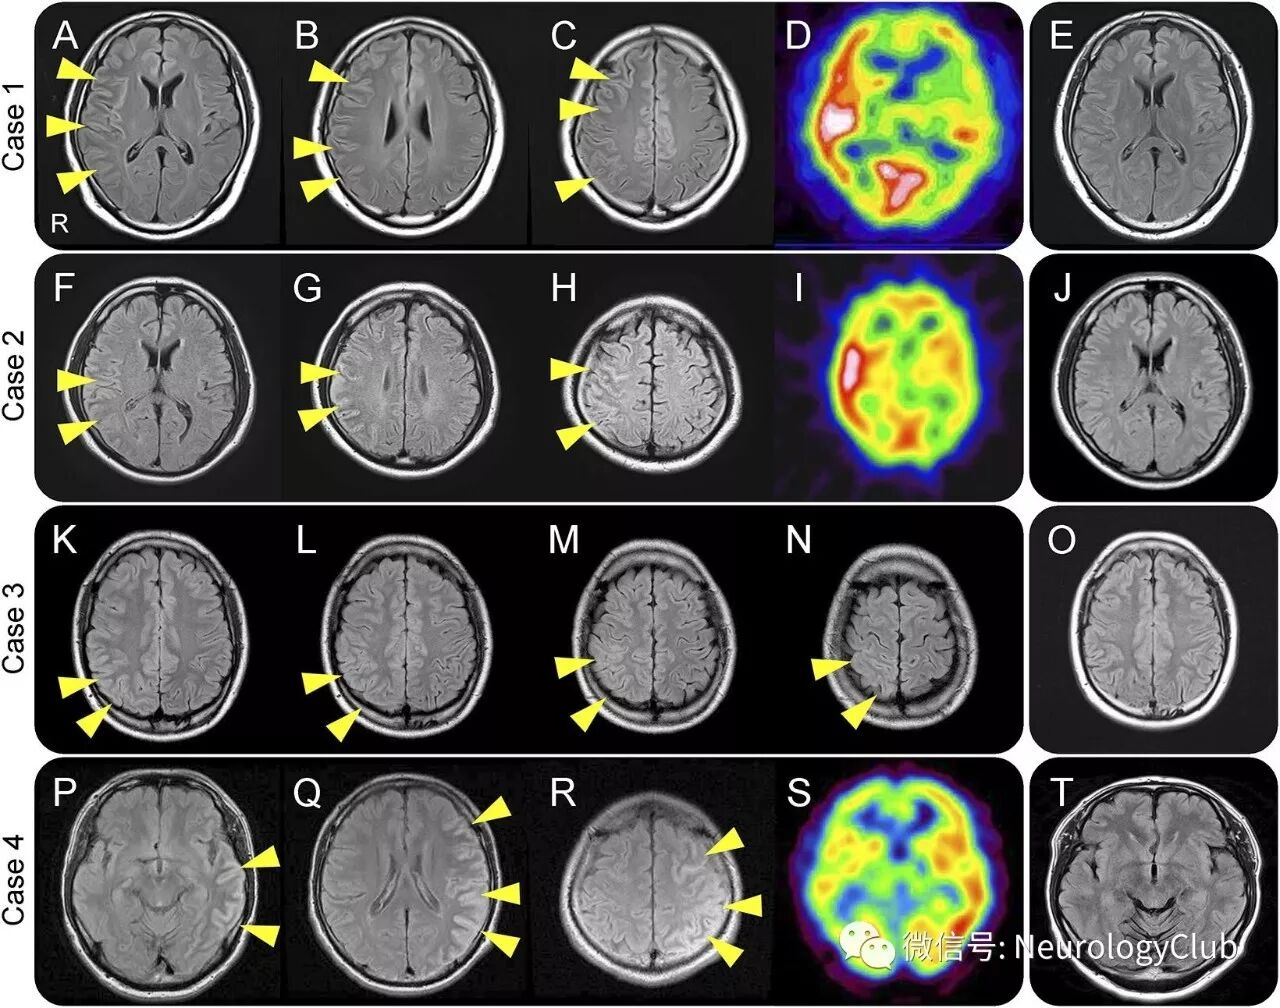

除了病例1外,还发现3例血清MOG抗体阳性的病例。4例患者的临床特征见表1。所有患者均为男性,平均发病年龄为34岁(23-39岁)。均有癫痫发作,3例出现行为异常,2例出现ON(图1),1例出现排尿困难,没有患者存在脊髓病变。脑脊液(CSF)检查平均细胞数为83/μL(平均为29-311/μL),平均蛋白浓度为46mg/dL(35-86mg/dL)。3例(病例1-3)患者的CSF行MOG抗体检测,结果均阳性,但无髓鞘碱性蛋白(Myelin basic protein,MBP)增加。4例患者均行头颅MRI检查,FLAIR上可见单侧大脑皮质高信号病灶(图2-3)。本组研究中其他MOG抗体阴性的病例均未出现如上的MRI改变。4例患者接受静脉注射大剂量糖皮质激素并给予抗癫痫药物治疗后完全恢复。同时检测了其它脑炎相关的抗体(AQP4、NMDAR、AMPA、LGI1、CASPR2、GABAb),但结果均为阴性。

(图3:入院时病例1[A-C],病例2[F-H],病例3[K-N],病例4[P-R]可见单侧皮质FLAIR高信号[箭头];病例1,病例2和病例4脑SPECT提示FLAIR高信号病灶区高灌注[D,I,S];至少随访2年后复查头颅MRI,皮质FLAIR高信号病灶消失[E,J,O,T])

4例患者的单侧皮质损伤需要与癫痫导致的脑部MRI异常鉴别。癫痫发作导致的脑部MRI异常一般局限于皮质/皮质下区、海马、基底节、白质或胼胝体,因细胞毒性水肿常在DWI上呈高信号。但本组病例中,FLAIR比DWI和ADC显像更清晰。CSF细胞数增多、大剂量激素治疗有效提示该特殊的单侧皮质病变为炎症性,SPECT上的高灌注与皮质FLAIR高信号相对应,支持炎症本质以及急性期肿胀的皮质病变导致的癫痫发生。